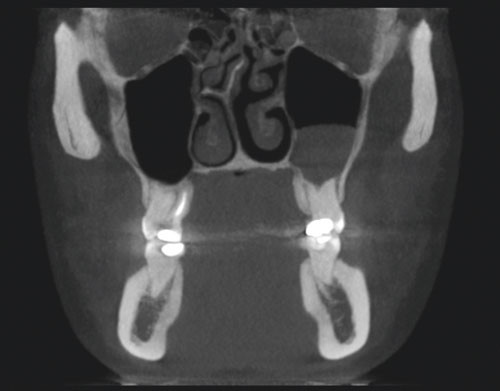

E-figur 3 og 4 viser CBCT-bilder av anatomiske strukturer i nese, maksille, strupehode og svelg. Det todimensjonale bildet viser retensjonspolypp i venstre maxillarsinus (e-fig 3), men det ble ikke funnet luftveispatologiske forandringer i strupehodet eller svelget (e-fig 4).

e-fig 3 og e-fig 4 finnes kun i Tidsskriftets nettutgave.